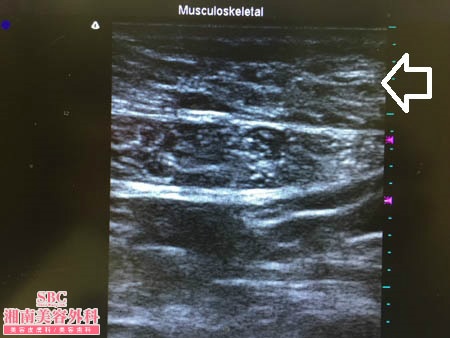

No.176730【脂肪吸引】【動画あり!】湘南美容外科脂肪吸引最高責任者である竹田先生による脂肪吸引!産後に20kg体重が増加してしまった患者様のおなかの脂肪吸引!術中3Dタッチビュー・上腹部

術中3Dタッチビュー

3Dタッチビュー(=超音波)で

皮下脂肪層の変化を見てみましょう。